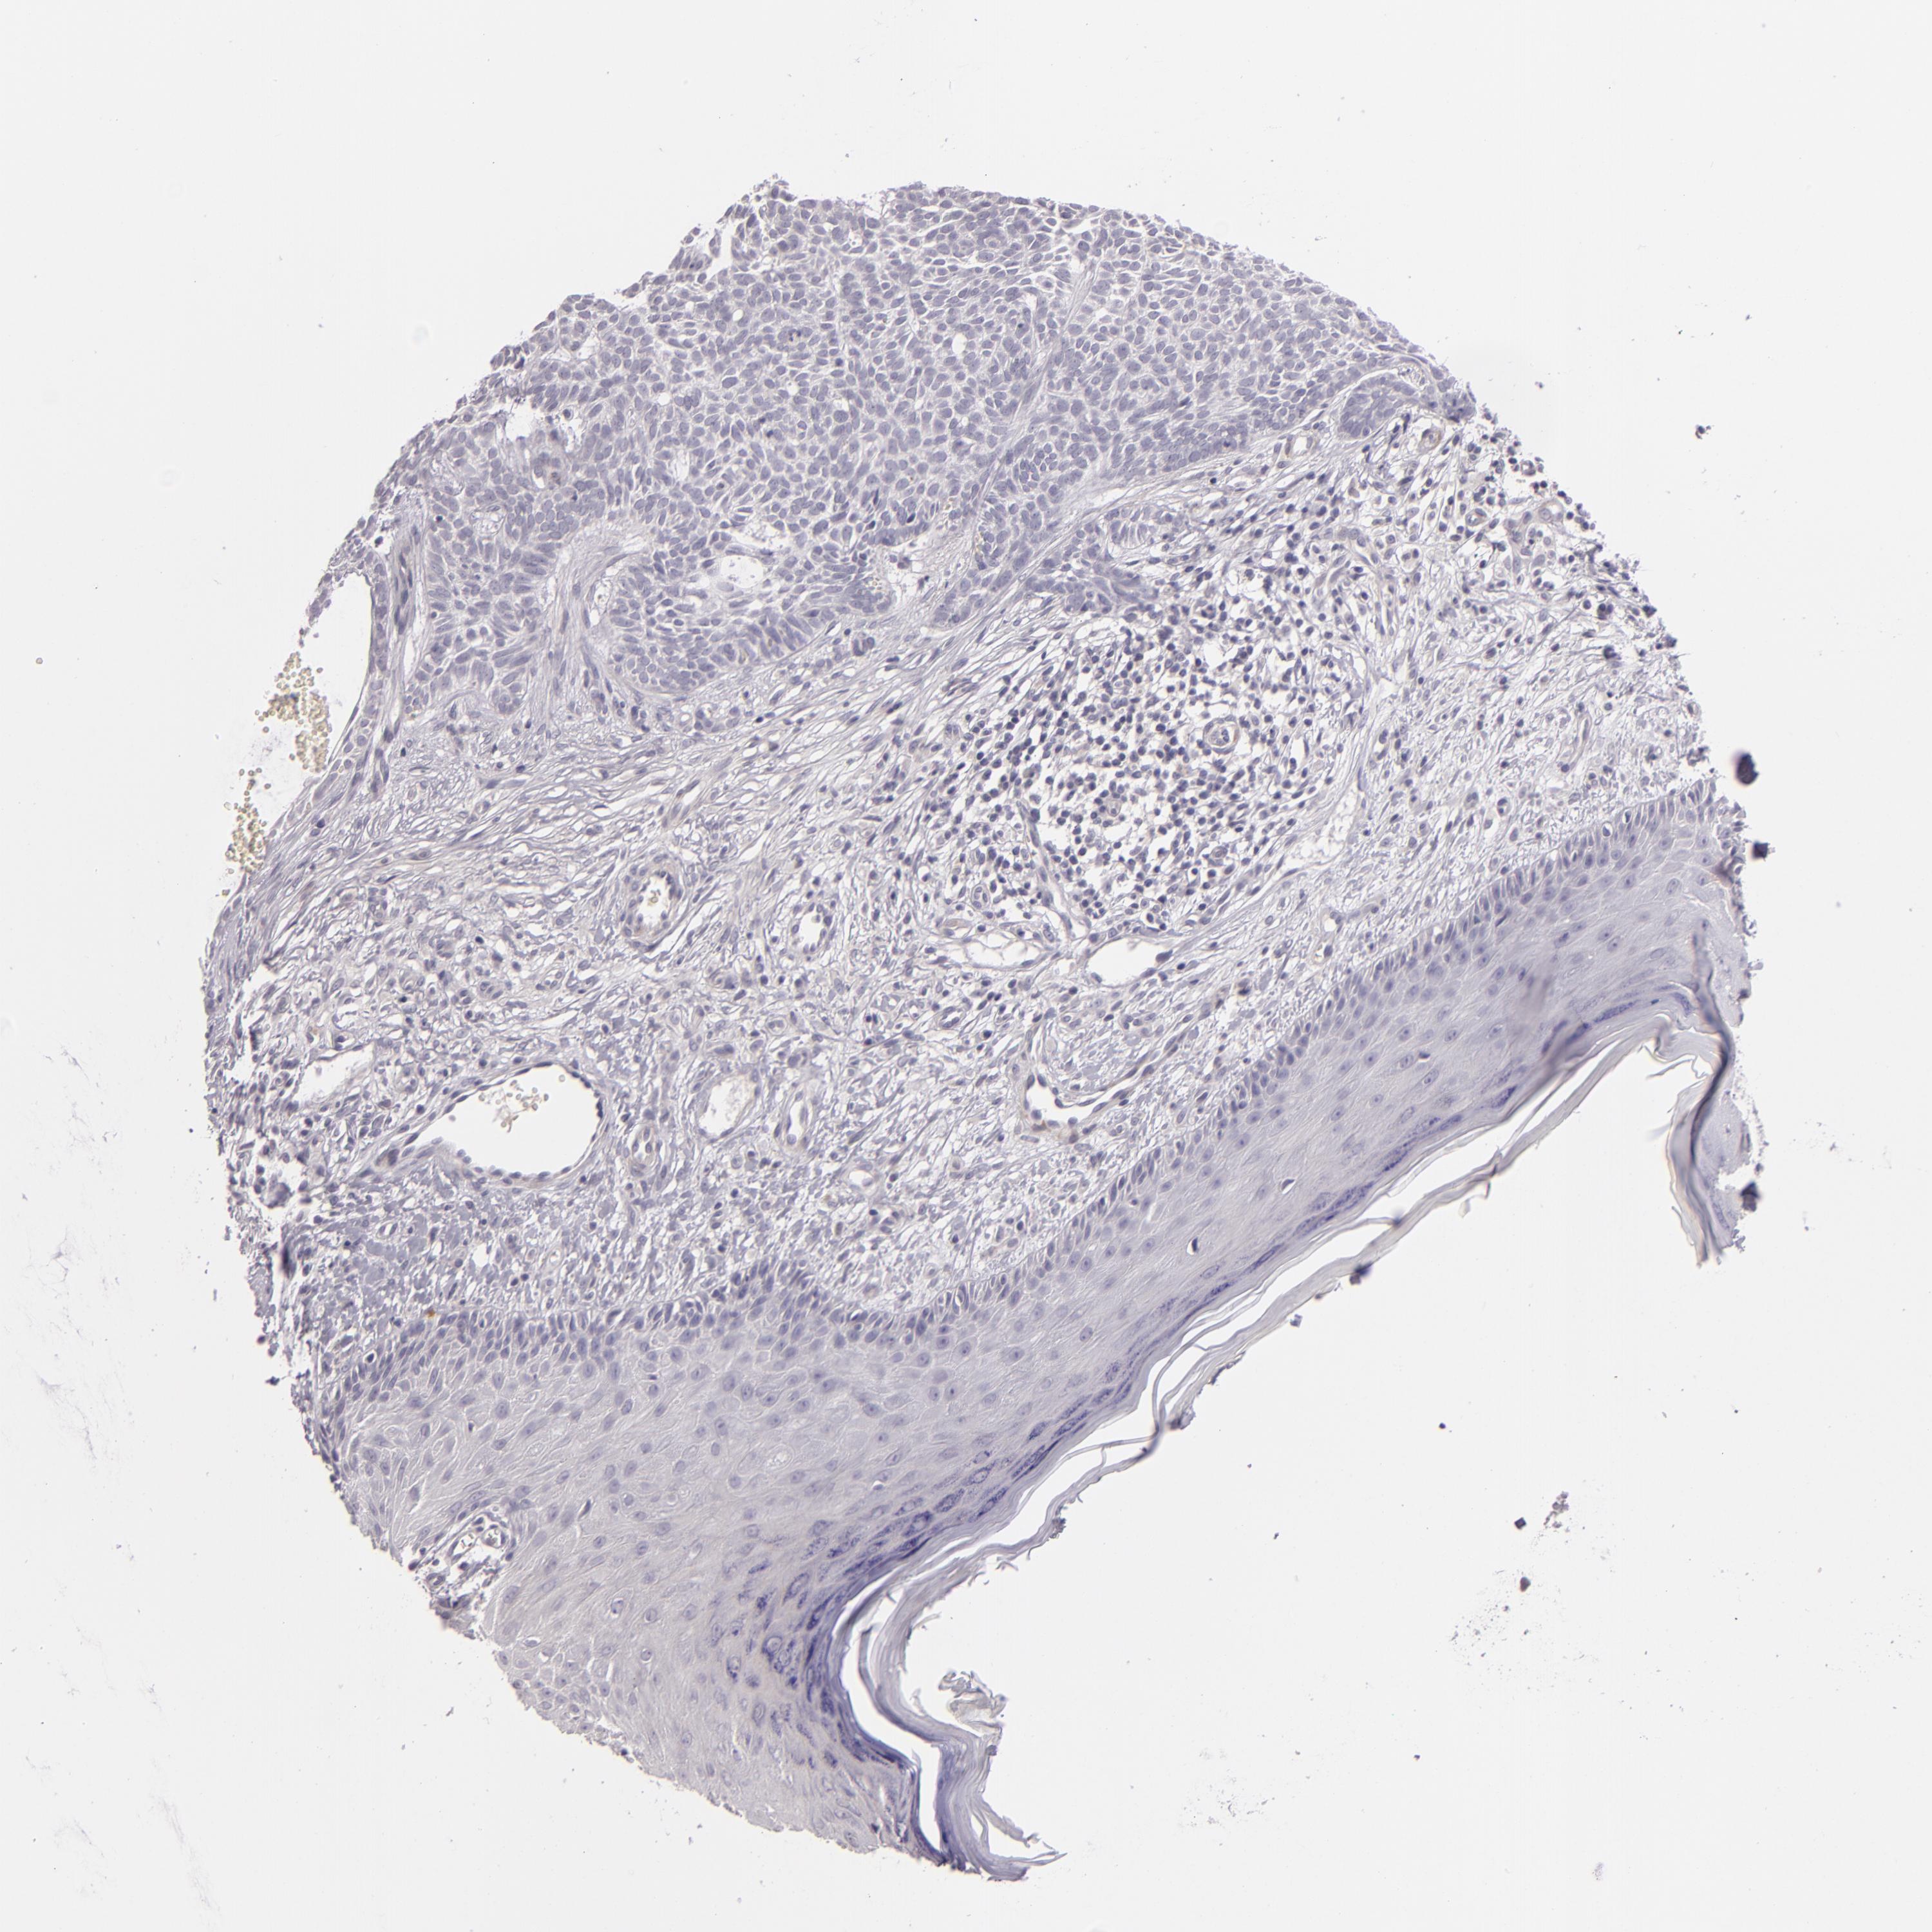

Basal cell and squamous cell cancer

SKIN CANCER - Protein expressioni

A mouse-over function shows sample information and annotation data. Click on an image to view it in a full screen mode. Samples can be filtered based on level of antibody staining by selecting one or several of the following categories: high, medium, low and not detected. The assay and annotation is described here.

Antibody stainingi

Antibody staining in the annotated cell types in the current human tissue is reported as not detected, low, medium, or high, based on conventional immunohistochemistry profiling in selected tissues. This score is based on the combination of the staining intensity and fraction of stained cells.

Each image is clickable and will lead to virtual microscopy that enables deeper exploration of all samples and also displays staining intensity scores, fraction scores and subcellular localization as well as patient and tissue information for each sample.

Antibody HPA001838

Squamous cell carcinoma, NOS

Basal cell carcinoma